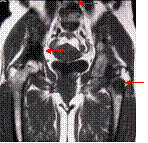

Metastatic deposits

Breast cancer and hip pain